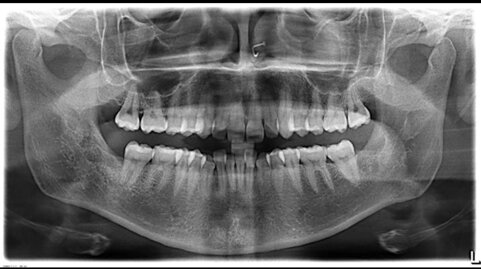

L'ortopantomografia evidenzia gli ottavi superiori in normoestrusione, mentre gli ottavi inferiori appaiono inclusi in mesioversione quello di destra e in distoversione quello di sinistra